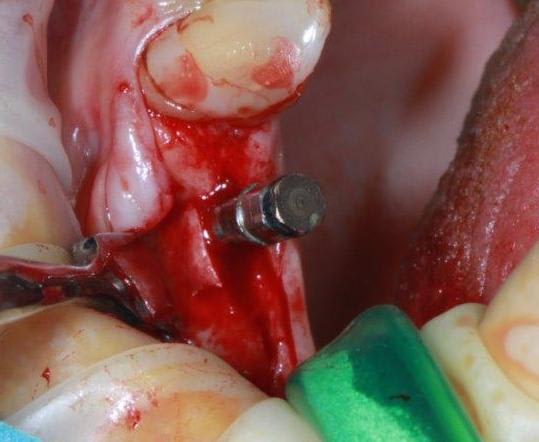

un petit cas pour ressortir ce post...et parce que c'est quand même chaud

incision crestale lame n°15, tatum, spreader Meissinger implants, PX34120 et OP34100 (summer avec eponges)

par contre je fais pas mal de radios, exemple spreaders trop près de la racine donc changement d'axe (d'où l’intérêt de l'expansion)